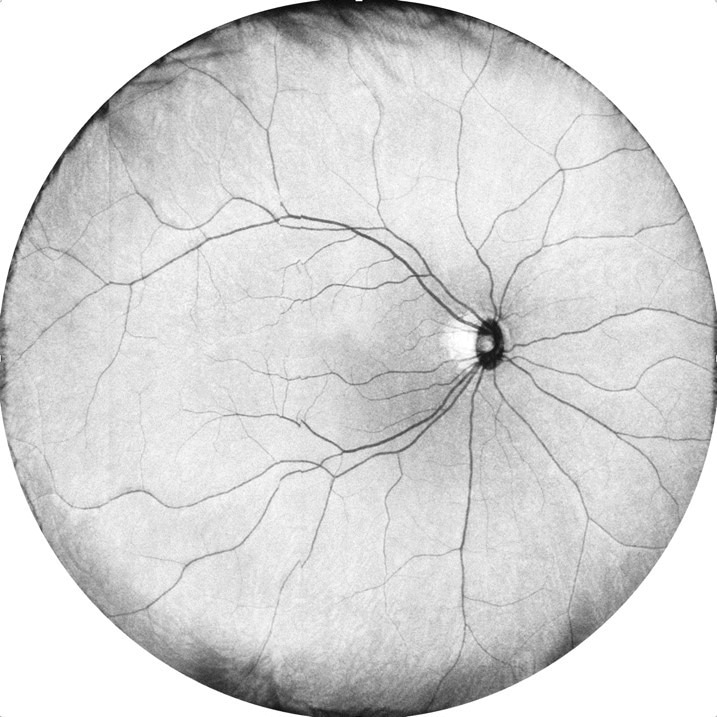

The evolution of OCT for retinal imaging and disease intervention

Image Credit: Dr. Jian, OHSU University